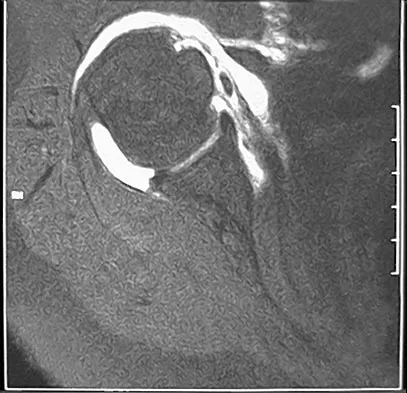

A 39-year-old man has anterior shoulder pain after landing on his abducted left shoulder while playing softball. Examination reveals a stable glenohumeral joint, pain on passive external rotation of greater than 25 degrees, and pain and weakness on belly press (Napoleon's) test. An MRI scan is shown in Figure 32. To provide maximum pain relief and return of function, management should include